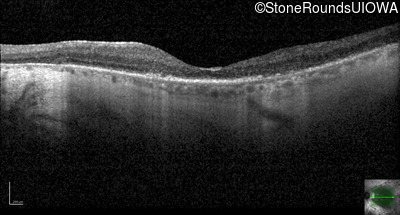

Optical Coherence Tomography - Right - 20/63 -2

Exemplar / OCT Stack